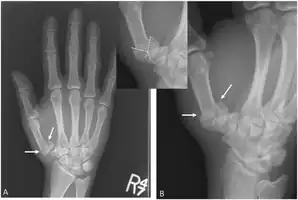

| Rolando fracture - a comminuted intra-articular fracture of the first metacarpal bone. | |

The cause is generally a force along the long axis of the thumb, such as during a fight.[3][4] Diagnosis is by medical imaging; such as X-ray, CT scan, or MRI.[3] It results in at least three bone fragments, which often form a T- or Y-shaped pattern.[3][4] It differs from a Bennett fracture which only results in two bone fragments.[4]

'Y-shaped' Rolanda fracture